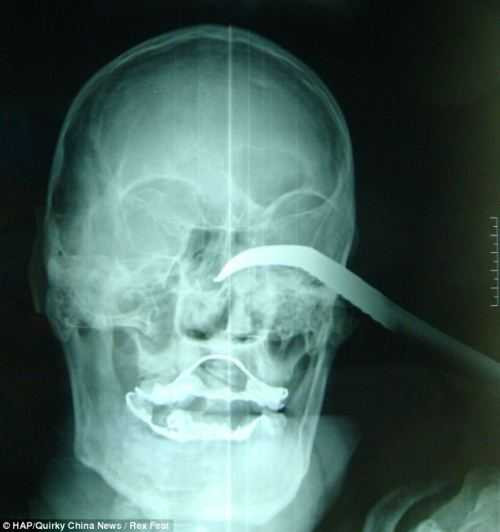

Kết quả chụp X-quang cho thấy thanh sắt nhọn lún tới 5 cm trong hốc mắt nạn nhân. Kinh khủng hơn, một hình ảnh chụp lại cho thấy ông Wang ngồi giữ thanh sắt trong đau đớn để tránh việc nó gây ra thương tổn nặng hơn.

| Hình ảnh chụp Xquang móc sắt đâm sâu vào hộp sọông Wang |

Hốc mắt người đàn ông phình ra theo toàn bộ đường cong của chiếc móc, máu khô đóng lại trên khắp khuôn mặt ông Wang.